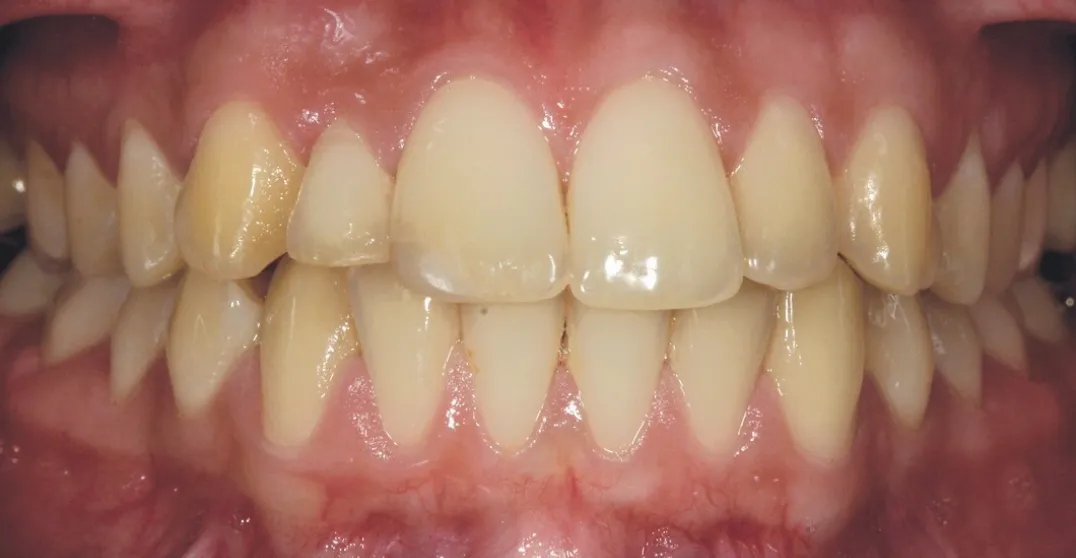

2 号病例 - Patrick EXBRAYAT 医生(图 21 至 35)

22 岁患者,23 异位,行正颌外科种植术后 22 出现严重根吸收。

图 33 :最终完成,自然微笑。